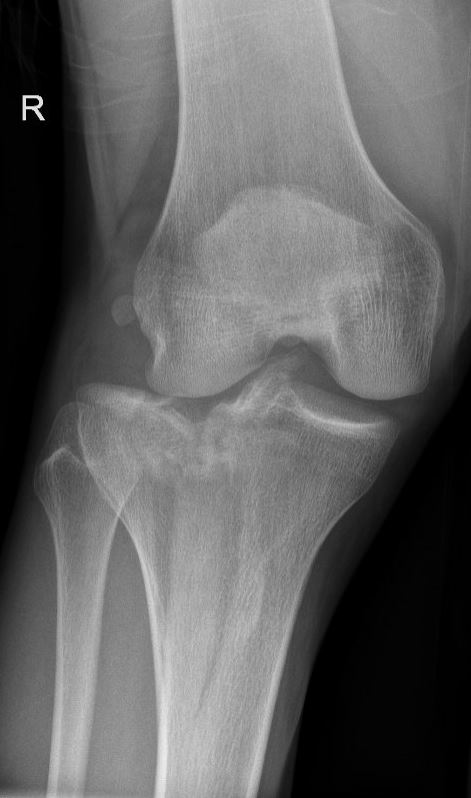

Het tibia plateau

Het plateau van de knie (ook genoemd ‘tibia plateau’) is het dragende gedeelte van het scheenbeen (de tibia) dat samen met het dijbeen het kniegewricht vormt. Het plateau van de tibia is bedekt met kraakbeen en vormt zo een glad gewrichtsoppervlak. In het midden van het plateau zitten de kruisbanden die richting het dijbeen gaan en aan zowel de binnen als de buitenkant ligt een meniscus.

De breuk

Een breuk van het tibia plateau ontstaat door fors inwerkend geweld, vaak door een verkeersongeval of val van hoogte, waarbij de knie meestal geforceerd naar binnen of naar buiten beweegt. Daarmee komt er zoveel druk op het plateau dat deze het begeeft en aan de binnen of buitenkant (of beide) breekt. Hierbij zakt dat gedeelte van het plateau vaak in. Naast het bot raakt dan ook altijd het kraakbeen beschadigd, maar vaak ook de meniscus of zelfs de kruisbanden.